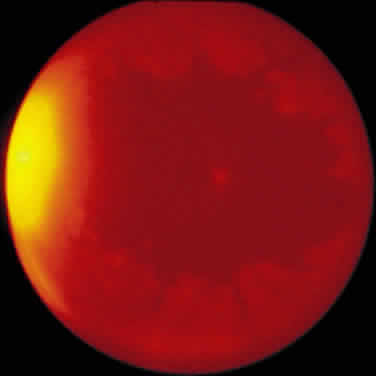

ARN is characterized by a retinal vasculitis affecting both the arteries and veins in the fundus, which is manifested by sheathing of the larger vessels (Fig. 2).7–10,16 Initially, patchy areas of peripheral retinal whitening (“thumbprint lesions”) representing full-thickness retinal necrosis are present or develop shortly after the vasculitis (Fig. 3). During a course that may span days or weeks, these patches coalesce into geographic areas (Fig. 4A). The entire peripheral retina (360 degrees) may be involved, or, more commonly, there are several noncontiguous patches of necrosis, each covering from a half to three clock hours (Figs. 5 and 6). The posterior segment lesions may not be detected without examination of the peripheral retina.

As the infection progresses, the leading edge of confluent retinal whitening advances toward the posterior pole (Fig. 7A). The retinitis may not progress posteriorly to the vascular arcades, sparing the macula and central vision. It is hypothesized that the retinal necrosis in ARN results from the combined effect of intracellular viral replication with subsequent cell death and vascular occlusion secondary to acute vasculitis. In some patients, the retinal vasculitic component may be much more prominent than the retinal necrosis.7 Optic disc swelling, either hyperemic or pallid, is a common feature of the ARN syndrome.1 Perivascular hemorrhages may be present (Fig. 8); however, widespread areas of retinal hemorrhage are atypical. Retinal vascular occlusion, often involving the arteries, can occur at any point during the clinical course. Without treatment, the inflammatory component of ARN typically burns out in 6 to 12 weeks, leaving behind a thin atrophic retina with associated pigmentary changes.10